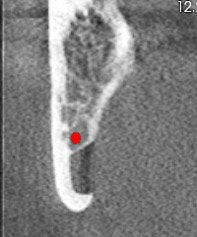

Figure 3: Coronal view of the posterior right mandible (the inferior alveolar canal is highlighted by red dot).

There is a hypodense lesion (radiolucent) that is well-defined, well-corticated, oval in shape, 8 x 6 mm, located at the posterior right mandible, and distal to tooth #32. The lesion is located below the inferior alveolar canal. No expansion is observed in the cross-sectional views. No calcifications are observed inside the lesion.

From the radiographic perspective, Stafne bone defects are radiolucent lesions, well-defined and well-corticated, oval in shape, and located below the inferior alveolar canal. No expansion is usually observed in the coronal views.

The differential diagnosis includes benign and malignant lesions; however, the location below the inferior alveolar canal is an anatomical landmark that helps to differentiate a Stafne bone defect from odontogenic lesions (usually located above the inferior alveolar canal).